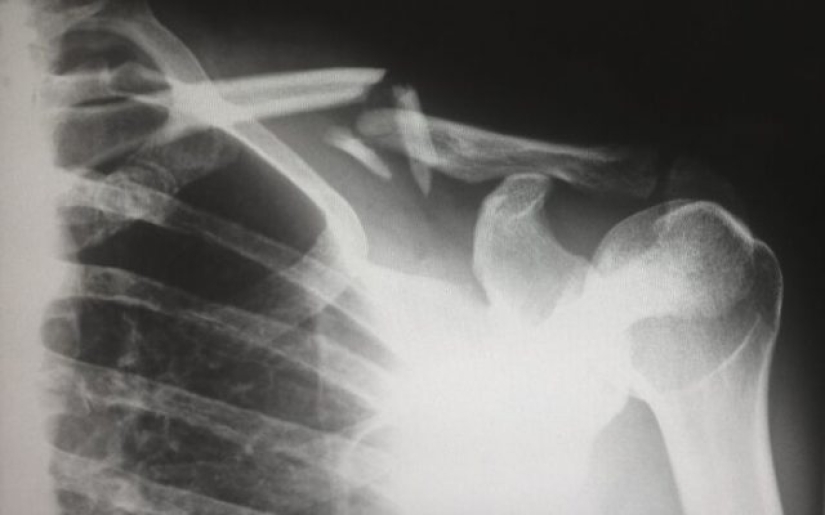

1. Cuando la tecnología de rayos X estuvo ampliamente disponible para los pediatras, notaron una asombrosa cantidad de huesos rotos. Los médicos, desconcertados, han sugerido que esta es la primera vez que se observa en niños una enfermedad ósea previamente desconocida. Resulta que no teníamos idea de lo común que era el abuso infantil.